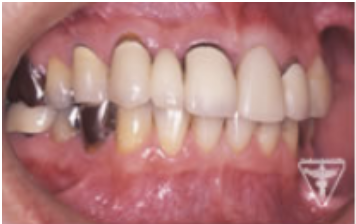

治療後

初期治療を経て歯周外科、歯内療法により病巣の消失が認められ改善された。

右上は将来人工歯根による処置の為GBRを行った。

咬んだ感じが軽くなり、よく咬めると評価を頂きました。